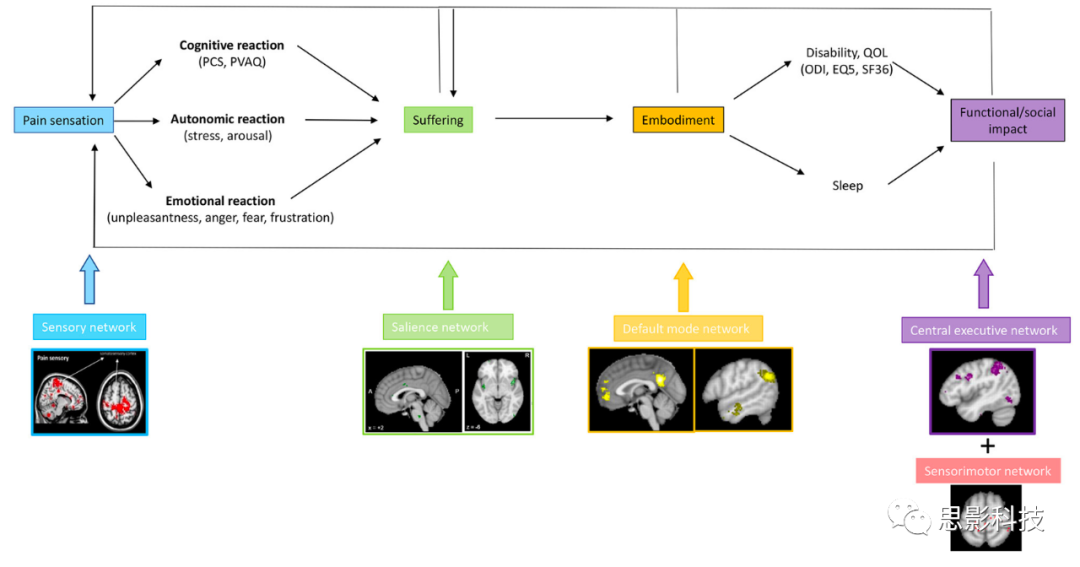

疼痛刺激通常会导致负面的认知、情感和自主反应,表现为由中央通路处理的与疼痛相关的痛苦。这在解剖学上与编码疼痛刺激的行为相关性和中央交感控制网络的突显网络重叠。当疼痛持续的时间超过愈合时间并变成慢性时,与疼痛相关的体感皮层活动可能会与自我表征的默认模式网络功能性地连接,即,它成为自我感知的固有部分。这很可能是为了节省能量而进行的进化适应,通过将疼痛与消耗交感能量的行动分开。通过与前额顶叶中央执行网络的相互作用,这最终可能导致功能障碍。

因此,从解剖学和症状学角度来看,慢性病理性疼痛可以分解为三个可分离但相互作用的通路,包括一个侧向的“疼痛感”通路,一个中央的“痛苦”通路,以及一个下行的疼痛抑制通路(25, 27, 28)(图2,图3)。尽管侧向体感和中央突显通路可以解释疼痛的疼痛感和情感成分,但尚未提出与慢性疼痛中遇到的慢性化和功能障碍相关的因素。我们建议将当前的疼痛网络扩展到三重网络模型以填补这一空白。

三重网络模型是一种基于网络科学的方法,用于研究认知和情感障碍(30)。它声称,神经精神疾病是由三个关键大脑网络内部和之间的异常互动引起的。这三个网络包括自我表示的默认模式网络(31, 32),它最初由Raichle在2001年描述(33);行为相关性编码的突显网络(34)和目标导向的前额顶叶中央执行网络(34, 35),两者均由Seeley在2007年确定(34)(图4)。通常,中央执行网络和突显网络显示相关活动,而这两个网络与默认模式网络呈反相关(36)。突显网络作为默认模式网络和中央执行网络之间的开关(37-39)。这与这三个网络的提议功能是一致的。当突显网络识别到一个外部行为相关的事件时,它会减少以自我为中心、思绪漫游的默认模式网络的活动,并激活外部目标导向的中央执行网络来处理外部显著刺激。这三个关键网络内部和之间的功能连接在许多大脑障碍中都是异常的,包括抑郁症、焦虑症、精神分裂症和创伤后应激障碍(30)。我们提议,在慢性疼痛中,已知的三个疼痛通路可以扩展到三重网络模型,这将解释疼痛的慢性化以及常见的认知功能障碍。

疼痛慢性化、能量消耗和默认模式网络

网络科学是一门研究复杂适应网络的科学,这些网络包括电信、计算机、经济、生物、社会、认知和语义网络,通过将它们分解为节点(或顶点)和连接(或边)。使用网络科学来研究大脑障碍(如慢性疼痛)中静息态网络连接的作用越来越普遍(123-126)。其中一个发现是默认模式网络在慢性疼痛中的参与(127-129)。疼痛存在的时间越长,初级感觉皮层与默认模式网络之间的连接就越强(128)。这一机制似乎是普遍的,因为它适用于CRPS、慢性背痛和骨关节病疼痛(128)。控制自我表征处理的默认模式网络被认为在慢性疼痛中与引发疼痛的网络病理性地耦合(130)。这一发现的重要性是巨大的,因为它可能为慢性疼痛变得与自我身体化,即成为自我的一个不可分割的部分,从而使治疗更加困难,提供了一种神经生物学解释。当痛苦是慢性的时,不仅疼痛可能成为一个人身份的一部分,而且恐惧可能发展为担忧/焦虑,悲伤可能发展为抑郁。在持续的焦虑中,杏仁核与DMN的背内侧前额叶皮层耦合(131, 132),而持续不灵活的悲伤在抑郁症中表现为膝下前扣带回皮层与默认模式网络中的pgACC-rACC之间的功能连接增加,与对照组相比(133)。

疼痛、认知功能障碍与中央执行网络

慢性疼痛可能导致痛苦,从而可能导致生活质量下降和与疼痛相关的身体和认知障碍的发展(76, 81, 146)。基于网络科学原理,可以设想疼痛的每个方面都是侧路,即感觉运动网络,与另一个静息态网络(如突显网络(痛苦)、默认模式网络(具身化)和中央执行网络(认知障碍)以及运动网络(身体障碍))之间的连接性变化的结果(图7)。患有失败性背部手术综合症(147)、偏头痛(148)和下背痛(130)的患者的特点是感觉运动、突显、默认模式和中央执行网络发生变化。然而,在这些研究中,没有进行相关性分析以将这些网络变化与临床症状或合并症联系起来,从而限制了对这些变化意味着什么的解释。默认模式网络与健康受试者中与中央路径和压力网络重叠的突显网络呈负相关(36)。在慢性疼痛中,这种负相关性丧失(149)。实际上,慢性下背痛的特点是主要感觉运动皮层与默认模式和执行控制网络的超连接(130)。这些与感觉运动“疼痛感”网络和“痛苦”突显网络以及默认模式之间的体位联系仅限于疼痛身体区域的同质皮层表示(127)。这在逻辑上是有意义的,因为只有来自受损区域的疼痛才会成为自我的一部分,允许交感系统为身体其他部位的疼痛而被激活。疼痛与默认模式网络和突显网络的前岛叶之间的增加连接有关,这些通常是负相关的。这一概念表明,慢性疼痛与多个静息态网络的逐渐参与有关,需要进行将疼痛的特定临床特征与活动和连接性指标联系起来的研究。此外,如果这一假设是正确的,涉及有或没有痛苦、有或没有疼痛和痛苦的具身化以及有或没有障碍的患者的大规模研究可能是不合适的。从理论角度来看,可以假设在某一阈值以下的疼痛感,例如NRS为4-5,只会导致疼痛感,而没有痛苦。这将显示有限的网络激活的功能成像。当疼痛水平上升到6/10时,侧路和中央回路之间的功能连接可能开始引起痛苦。一旦疼痛达到更高的值,例如7/10,与中央执行网络的增加连接可能导致功能障碍。如果这一概念是正确的,就可以开发更为定制化的慢性疼痛治疗方法。

图 7:侧向感觉运动通路中疼痛刺激的存在,可以导致由中央突显通路编码的认知、情感和自主反应,表现为痛苦。当疼痛和痛苦变得慢性时,它们会变得具体化,即成为自我的一部分,通过感觉运动皮层与默认模式网络的连接来实现。具体化的疼痛和痛苦随后可能导致身体和认知障碍,可能是通过与运动和中央执行网络的功能失调连接分别进行的。

疼痛是由三个分开但相互连接的网络处理的,每个网络都编码了疼痛的不同方面。侧路,其主要中心是感觉运动皮层,主要负责疼痛感处理。痛苦成分与中央路径的参与有关,其中rdACC和岛叶是主要的中心,下行疼痛抑制路径可能与疼痛存在的时间比例有关。疼痛(感觉的完整性)可以在没有痛苦的情况下存在,痛苦也可以在没有疼痛(感觉的完整性)的情况下存在。当疼痛感觉路径与默认模式相关联而不是负相关时,疼痛就成为了自我感知的一部分。通过干扰以目标为导向的中央执行网络,疼痛可能导致功能障碍。因此,为了完全解释慢性疼痛的全面临床图像,必须将先前确定的三条疼痛路径扩展到包括三重网络。